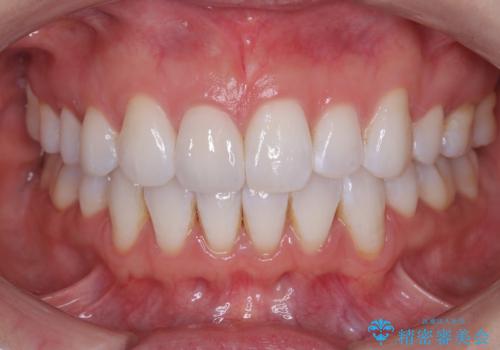

- 患者様は、前歯の被せ物の形や色が不自然で気になるというお悩みを抱えて来院されました。

診察の結果、既存の被せ物は古い素材で作られており、周囲の歯との調和が難しいことが分かりました。患者様とカウンセリングを重ね、アライナー矯正で歯列のガタツキを修正後、。より自然で審美的な仕上がりを目指してオールセラミッククラウンでの治療を提案しました。

オールセラミッククラウンは、金属を使用しないため、自然光の下でも透過性が高く、天然歯と見分けがつかないほど美しい仕上がりが得られる素材です。また、金属アレルギーの心配がなく、長期間使用しても歯ぐきへの影響が少ないという利点があります。